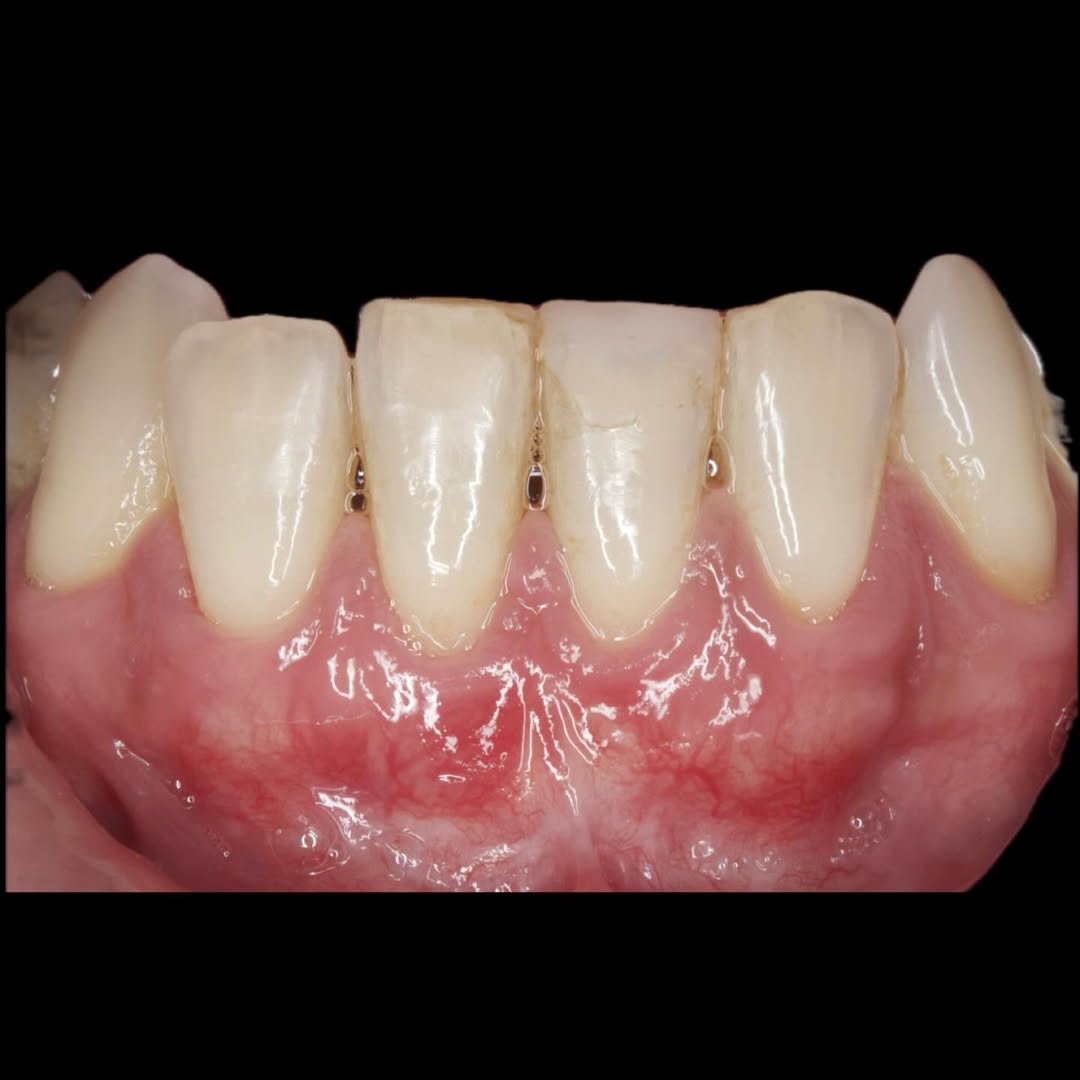

Aprende la planificación y técnica de la cirugía Mucogingival para el recubrimiento de recesiones y aumento de banda queratinizada en el sector anteroinferior

Durante una mañana, asistirás a una Cirugía Mucogingival de recubrimiento radicular de una recesión unitaria en 31 con frenillo asociado. Gracias al uso del microscopio y a la proyección en tiempo real en pantalla, verás exactamente lo mismo que veo yo durante la cirugía, sin tener que estar

Una estancia clínica pensada para quienes quieran iniciarse o dar un paso más en el campo de la cirugía mucogingival. Durante esta experiencia tendrás la oportunidad de aprender en directo cómo se planifica y se lleva a cabo una cirugía mucogingival mediante técnica de Túnel.

Una estancia clínica pensada para quienes quieran iniciarse o dar un paso más en el campo de la cirugía mucogingival. Durante esta experiencia tendrás la oportunidad de aprender en directo cómo se planifica y se lleva a cabo una cirugía mucogingival